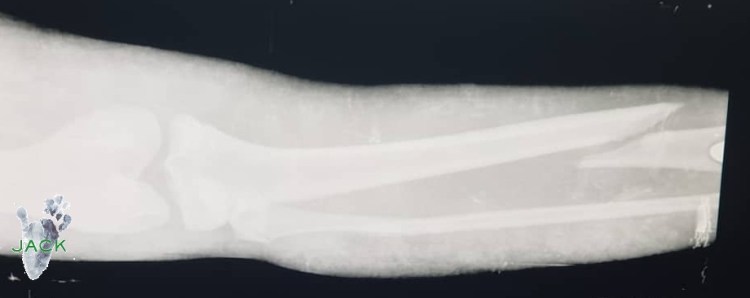

Pour ceux qui nous rejoignent, Bapu a cassé son tibia. Sans doute une mauvaise chute, on ne sait pas!

Le fait est qu’hier notre jeune amie a subi une longue intervention chirurgicale : 3 vétérinaires chirurgiens se sont penchés sur son cas pour lui placer une broche et des fils de cerclage.

Grâce à leurs expériences et leurs connaissances, la fracture a pu être opérée avec les moyens du bord car, je le rappelle, ici, beaucoup de choses font défaut et nous devons à chaque fois composer avec ce que l’on a, avec ce que l’on trouve! Pour Bapu, nous avons fait du mieux que l’on a pu!